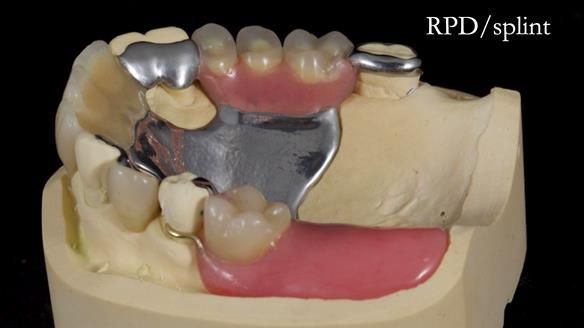

This edition features the case of Edgar, who sought help for a poorly fitting, acrylic-based partial denture that rocked, affected his speech, and caused discomfort. After considering various treatment options, including dental implants, Edgar opted for a metal-based removable partial denture, designed by myself with input from my technician, Rowan Garstang.

Treatment Process: I provided the clinical work while Rowan Garstang delivered the technical aspects. The treatment required fifteen visits to fit and review Edgar.